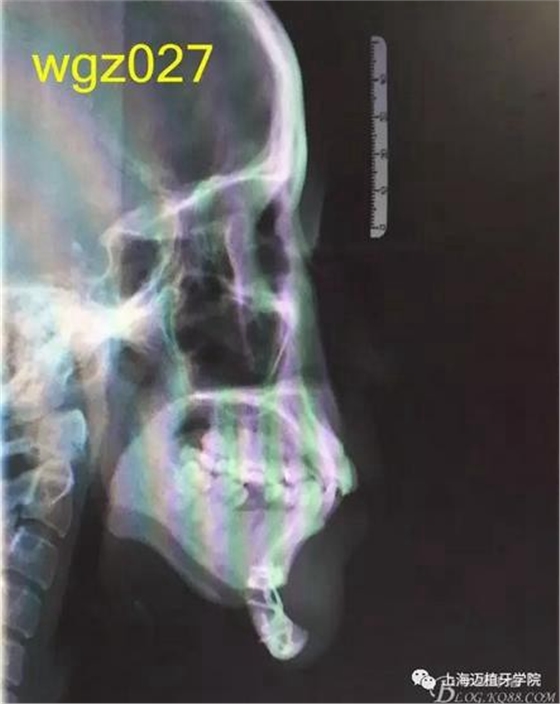

根據(jù)以下上傳的圖片及X線影像資料,你認為她的牙齒存在什么問題?應該如何進行矯治設計?

圖2

上海萬眾醫(yī)院正畸科進修醫(yī)生魏倩倩作業(yè)。 某女,25歲。 主訴:頦部術后自覺牙齒不齊,牙齒凸要求矯正。 既往史:曾有顳下頜關節(jié)疼痛史,于外院診斷為關節(jié)不可復性前移位伴髁突不對稱,行關節(jié)盤復位術。約3個月前在外院行頦成形術,現(xiàn)因牙齒不齊,牙齒凸前來就診。 口外檢查:正面觀,長面型,左右基本對稱,面下1/3過長,頦部明顯水腫,質硬; 側面觀,面型稍凸。 顳合關節(jié)檢查:無壓痛,左側彈響,兩側髁突運動基本一致。 口內(nèi)檢查:恒牙列,下頜前庭處縫合,傷口愈合良好??谇恍l(wèi)生情況一般,牙齦紅腫,LR2、LL6缺失,UR456舌傾與LR67成反合關系,UR3頰側突出移位,UR2UL2近中扭轉,UL1近中外翻唇傾,UR7UL7頰傾,LR6近中傾斜升高,LR5近中傾斜,LR4頰傾移位,LR3冠舌側傾斜,LL2近中扭轉冠頰傾,LL3舌傾,LL78近中傾斜。 模型分析:上頜前牙段擁擠度9.5mm,下頜前牙段擁擠度9mm,spee左右約3mm, LL5、LL7之間間隙約為5mm。上下中線右偏約1.5mm。全牙比約為80%,前牙比62%。磨牙關系:右側近中關系,UL6與LL7遠中尖對尖。尖牙關系:右側遠中關系,左側近中關系。 行為分析:患者已于外院行頦成形術,面型已改善,但患者仍覺得牙齒凸,說明患者非常重視面型問題,對美觀要求高。 頭顱側位片:面型稍凸,上唇在E線前約1.5mm,下唇在 E前約1mm 。 SNA: 85↑ SNB: 75↓ANB: 10↑ U1-L1: 113.6↓ U1-SN: 107.9 L1-M P: 88 ↓Y軸角:65.8 FH-MP: 37↑ SN -M P: 45↑ 曲面斷層片:28顆恒牙,LL6缺失,牙槽骨均位于釉牙骨質界以下,LR6、LL7近中牙槽骨角型吸收,頦部可見成型術鈦合板。左側升支較右側粗。 關節(jié)片:左右髁突不對稱,髁狀間隙右側明顯較左側寬,右側間隙清楚,大小勻稱 ,左側欠佳。 診斷:安氏3類 骨性2類 高角 上下前牙重度擁擠 中線不齊 間隙分析:下頜 , LL5與LL7之間的有5mm間隙,下頜擁擠度為9mm,整平下頜曲線需要約3mm間隙,下頜需要約12mm間隙,減去現(xiàn)有間隙還需要7mm間隙。上頜,擁擠度為9.5mm,擁擠主要集中在前牙段。 支抗分析:患者頦部術后仍覺面型凸(主要是上頜前突),所以除了要解決擁擠度外還需要內(nèi)收前牙,所以上頜需要強支抗?;颊逽NB為75,下頜發(fā)育不足,高角,相對低角病例來說,下頜磨牙較易前移。下頜前牙重度擁擠的情況下主張只解除擁擠不宜內(nèi)收(該患者系下頜后縮病例)。患者ANB為10°,本屬于正頜正畸聯(lián)合治療,現(xiàn)患者已做頦部成型術,患者面型得到改善,故患者現(xiàn)在主要為解決擁擠,少量內(nèi)收前牙,解決上前牙凸度。